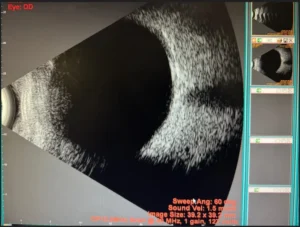

- ULTRASONOGRAPHY OF THE POSTERIOR SEGMENT

Ultrasound B-scan shows normal

A thick jelly is placed on the ultrasound probe by the retina specialist, which is then gently placed on the eye over the lid. It is a safe and painless procedure, no X-ray exposure occurs in this test. The retina specialist uses these echo pictures to arrive at a diagnosis, the probable future health of your eye, and a treatment plan. However, the test only reveals the structure of the inside of the eye.

ULTRASOUND OF RETINAL DETACHMENT

Ultrasound B-Scan shows retinal detachment